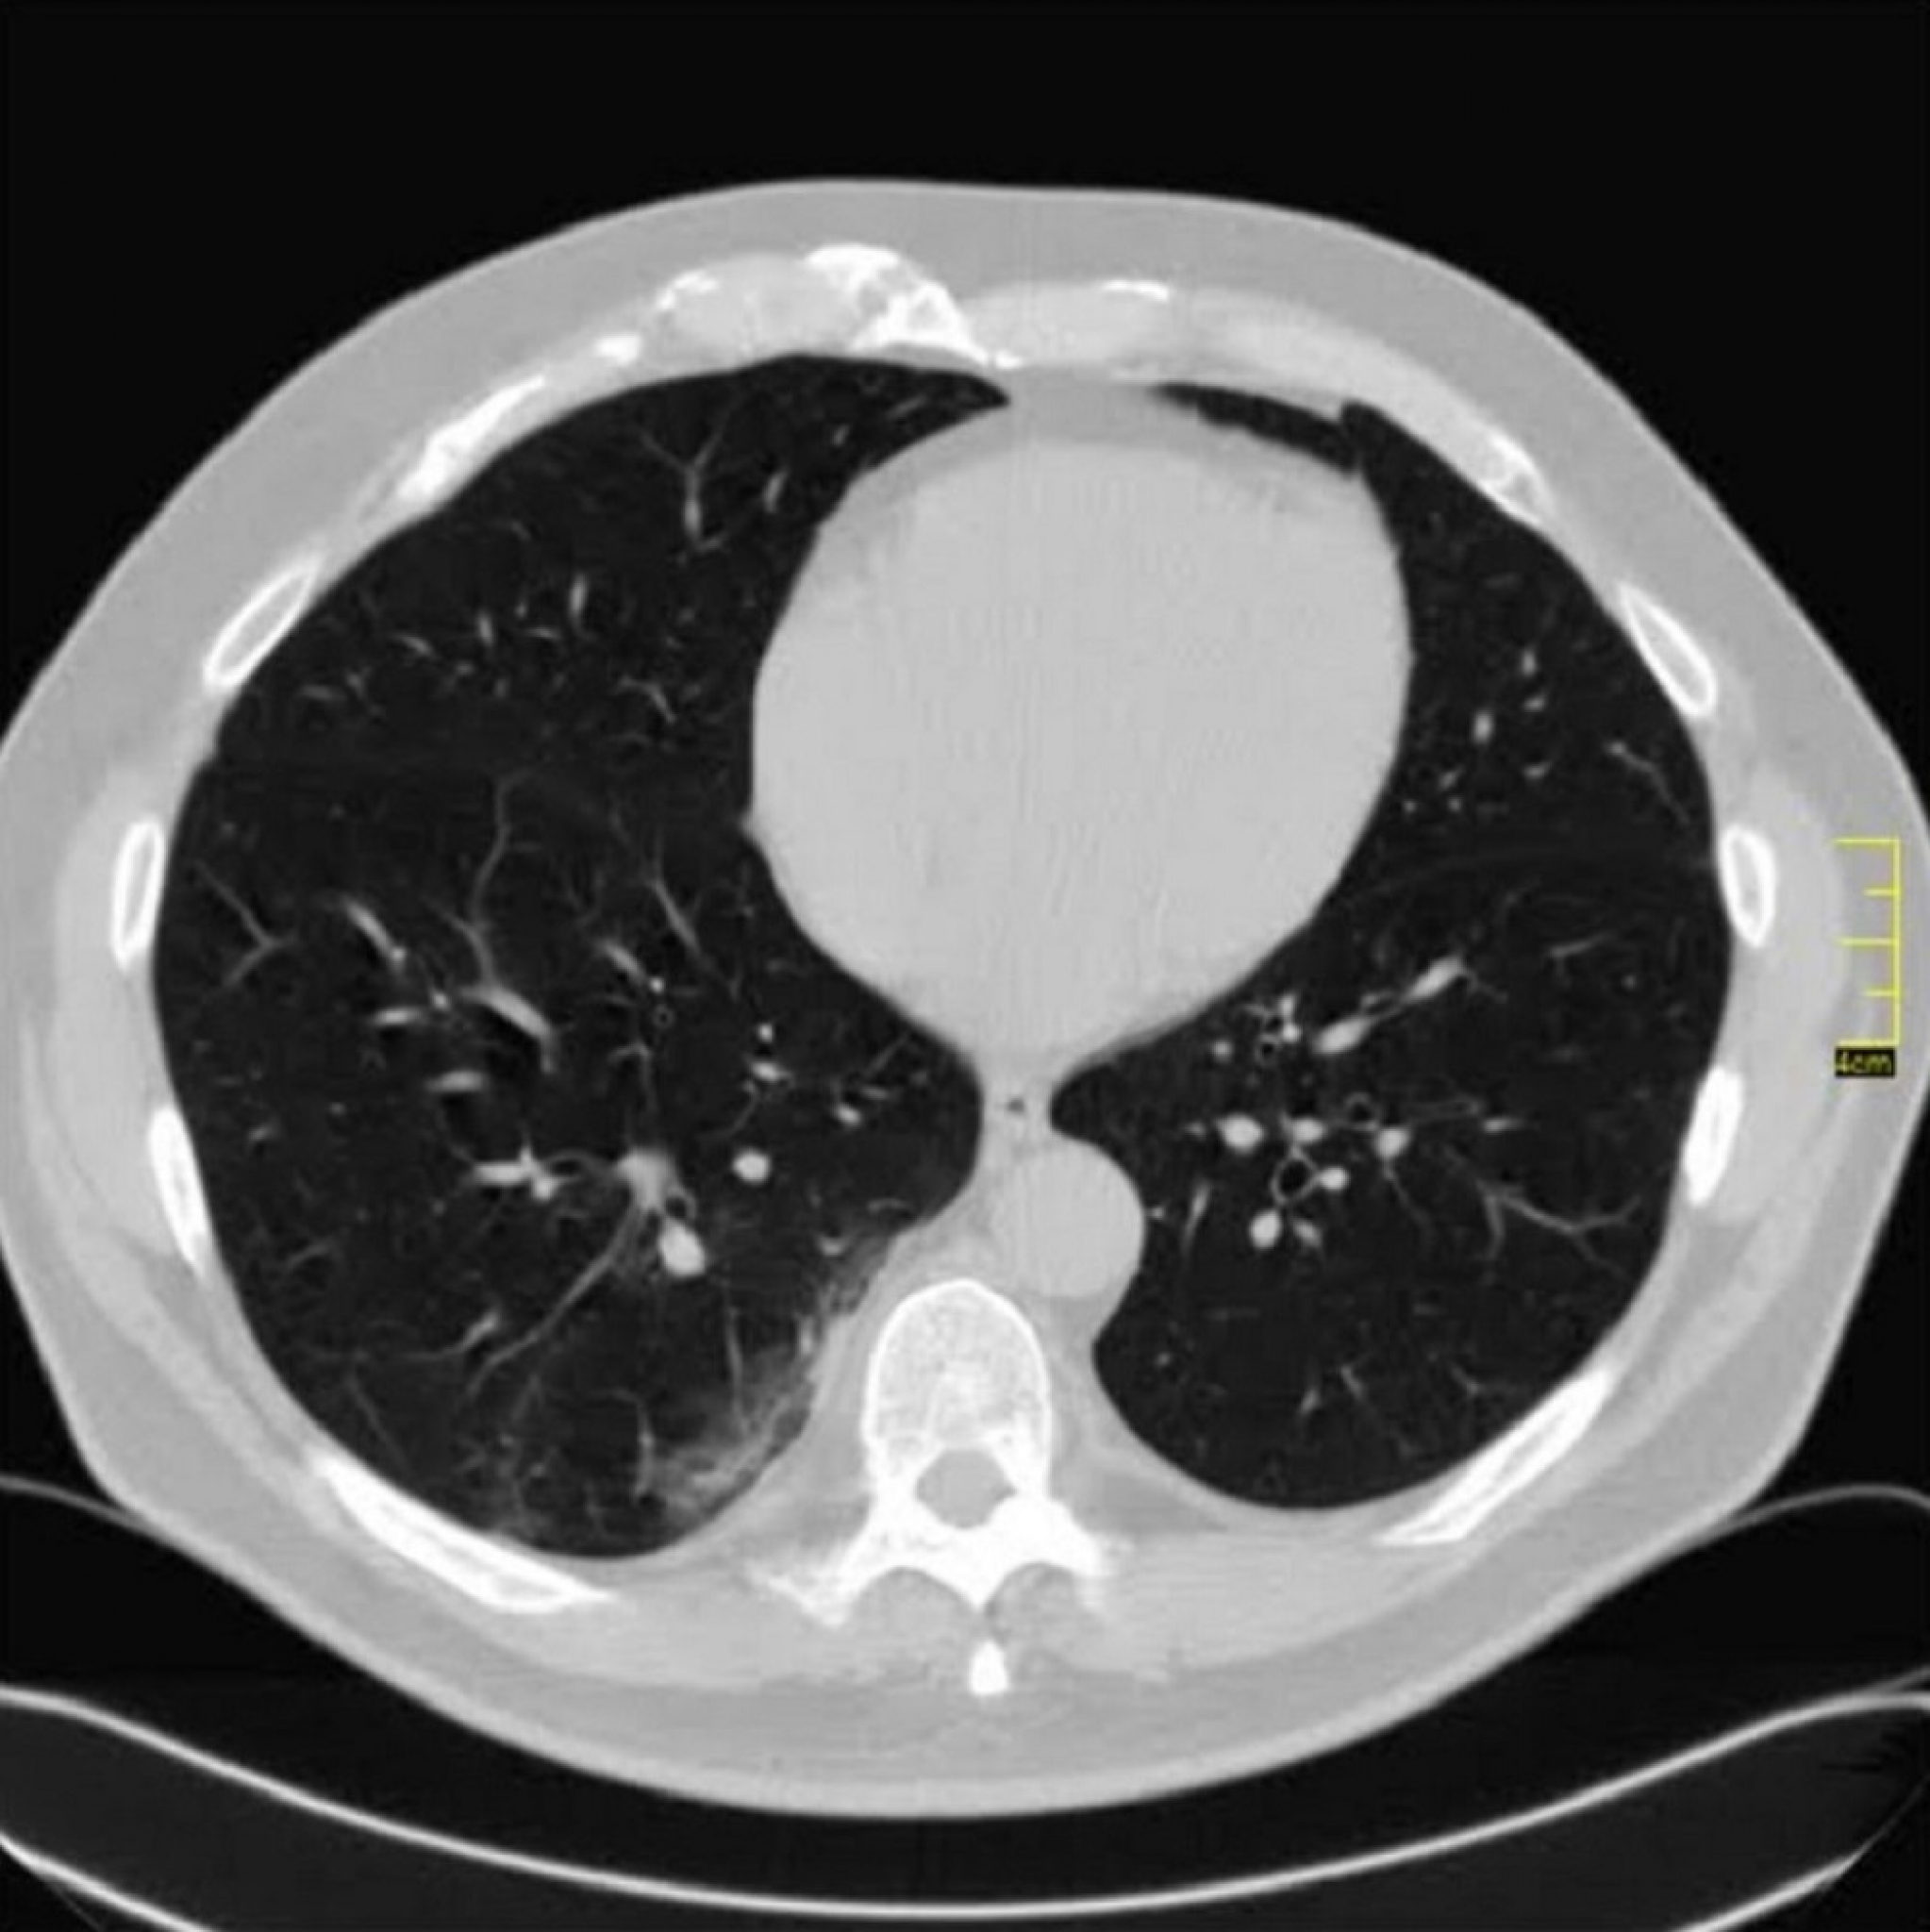

"Zadnjih deset dana se menja radiološki nalaz. Ne kod svih pacijenata, već kod jednog dela. Ali da krenemo redom.

Krenulo je sa divljim sojem. Znamo da je i on imao svoje varijante. Ono što je bilo u samom početku kod nas je ličilo na samu osnovu.

Kada se pogleda pažljivo i deluje divlje, nema neke pravilnosti.

Neki međusoj je bio u leto 2020. Decembar i januar je dominirao britanski soj. Kada se pogledaju njegove slike vidi se razlika u odnosu na divlji, a blizu je onoga koji je bio u leto 2020. godine.

Decembar, januar, februar, mart. 2020/21.

Gustina promena je različita, razlikovala se i klinička slika. retko u decembru ali do marta skoro isključiv.

April 2021. Počinju da dolaze pacijenti koji imaju drugačiji nalaz.

Ono što je karakteristično je to da su ovo nalazi koji su 2. i 3. dana bolesti u I fazi.

Znači ne u progresivnoj, već u uvodnoj fazi kada uglavnom nema CT znaka. Fibrozne trake već drugog dana? Ground glass oko većih grana bronha. Kao da bolest ne može da sačeka, kao da klija gde stigne.

Klinička slika se razlikuje od britanskog soja. To se slažu i moji pulmolozi. Za sada je desetak pacijenata (kod mene), malo za zaključke, ali to su pacijenti u kratkom vremenskom periodu od 31.03.2021. godine do 14.04.2021. godine.